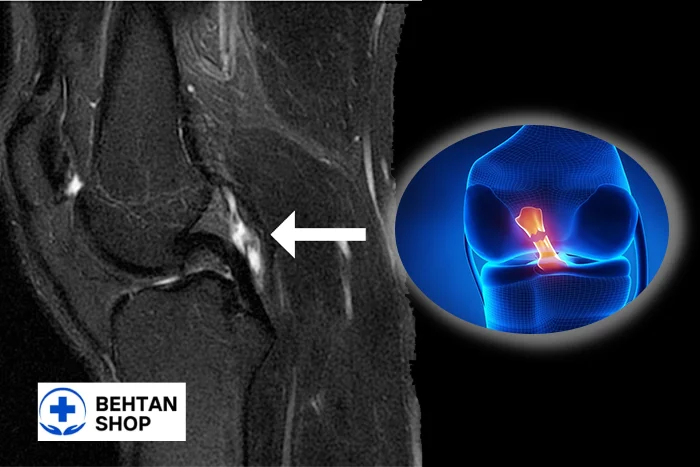

2. کیست منیسکی

یکی از ویژهترین انواع کیست زانو است و تقریباً همیشه با پارگی منیسک همراه است. این کیست در اثر ورود مایع سینوویال از طریق پارگی منیسک به بافت اطراف ایجاد میشود.

- محل ایجاد: کنار خط مفصل، بهخصوص در ناحیه خارجی زانو (Lateral meniscus).

- علائم: درد نقطهای شدید، تورم کوچک و سفت، تشدید درد با چرخش زانو یا نشستنهای طولانی. بیمار اغلب در هنگام فشار دادن همان نقطه، درد تیز و مشخصی احساس میکند.

- ویژگی مهم: کیست منیسکی بهتنهایی درمان قطعی ندارد؛ چون تا زمانی که پارگی منیسک اصلاح نشود، مایع دوباره به همان ناحیه نشت کرده و کیست تشکیل میشود.

- تشخیص: MRI بهترین روش برای تشخیص همزمان پارگی و کیست است.

- عوارض: اگر درمان نشود ممکن است باعث گیر افتادگی مفصل، قفلشدن زانو و تشدید پارگی شود.